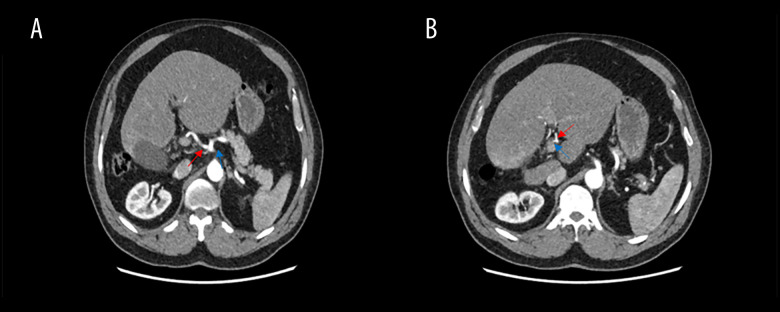

背景右肝叶发育不全是一种罕见的先天性异常,通常在影像学或外科手术中偶然发现。这种异常在手术中可能具有挑战性,导致术中并发症。右肝发育不全患者通常生活正常,无症状,但可合并肝硬化、门静脉高压症和胆结石。虽然先天性肝发育不全和胆囊炎之间的确切病理生理关系尚不清楚,但已经提出了一些促成因素。这些包括肝细胞核因子1B (HNF1B)转录的突变,胆囊功能受损以及由于位置不当导致的胆囊缺血。病例报告:一名70岁男性表现为坏疽性胆囊炎并并发右肝叶发育不全;以前没有记录的组合。患者最初无症状,表现为剧烈的胃脘痛,经腹部超声诊断为急性胆囊炎。然而,计算机断层扫描(CT)成像显示右肝叶严重发育不全,伴有左肝叶代偿性肥大,胆囊结石。尽管实验室结果正常,但我们认为这种异常延迟了诊断,直到发展为胆囊炎作为并发症。患者接受了成功的腹腔镜胆囊切除术,没有转到开放手术。结论:本病例强调了在计划手术时识别解剖变异的重要性。意识到右肝叶发育不全有助于及时诊断和适当处理,最终减少手术风险和并发症。此外,我们建议在急性胆囊炎症状不明确或不典型的情况下,以及腹部超声(US)显示胆囊位置异常时,进行CT检查。然而,我们建议在手术中确定解剖结构,以避免并发症。

BACKGROUND Hypoplasia of the right hepatic lobe is a rare congenital anomaly often discovered incidentally during imaging or surgery. This anomaly can be challenging during surgery, leading to intraoperative complications. Patient with right hepatic hypoplasia usually live normally without symptoms, but it can be associated with liver cirrhosis, portal hypertension, and gallstones. While the exact pathophysiological relationship between congenital hepatic hypoplasia and cholecystitis remains unclear, a few contributing factors have been proposed. These include mutations in the hepatocyte nuclear factor 1B (HNF1B) transcription, impaired gallbladder function, and gallbladder ischemia due to malposition. CASE REPORT A 70-year-old man presented with gangrenous cholecystitis and concurrent hypoplasia of the right hepatic lobe; a combination not previously documented. The patient, initially asymptomatic, presented with sharp epigastric pain and was diagnosed with acute cholecystitis through abdominal ultrasound. However, computed tomography (CT) imaging showed severe hypoplasia of the right liver lobe with associated compensatory hypertrophy of the left lobe in addition to stones in the gallbladder. Despite normal laboratory results, we think that the anomaly delayed the diagnosis until the development of cholecystitis as a complication. The patient underwent a successful laparoscopic cholecystectomy without converting to open surgery. CONCLUSIONS This case underscores the importance of recognizing anatomical variations when planning surgery. Awareness of right hepatic lobe hypoplasia can aid in timely diagnosis and appropriate management, ultimately reducing surgical risks and complications. Furthermore, we recommend performing CT in case of vague or atypical symptoms of acute cholecystitis, as well as when the gallbladder shows malposition on abdominal ultrasound (US). However, we recommend identifying the anatomical structure during the surgery to avoid complications.